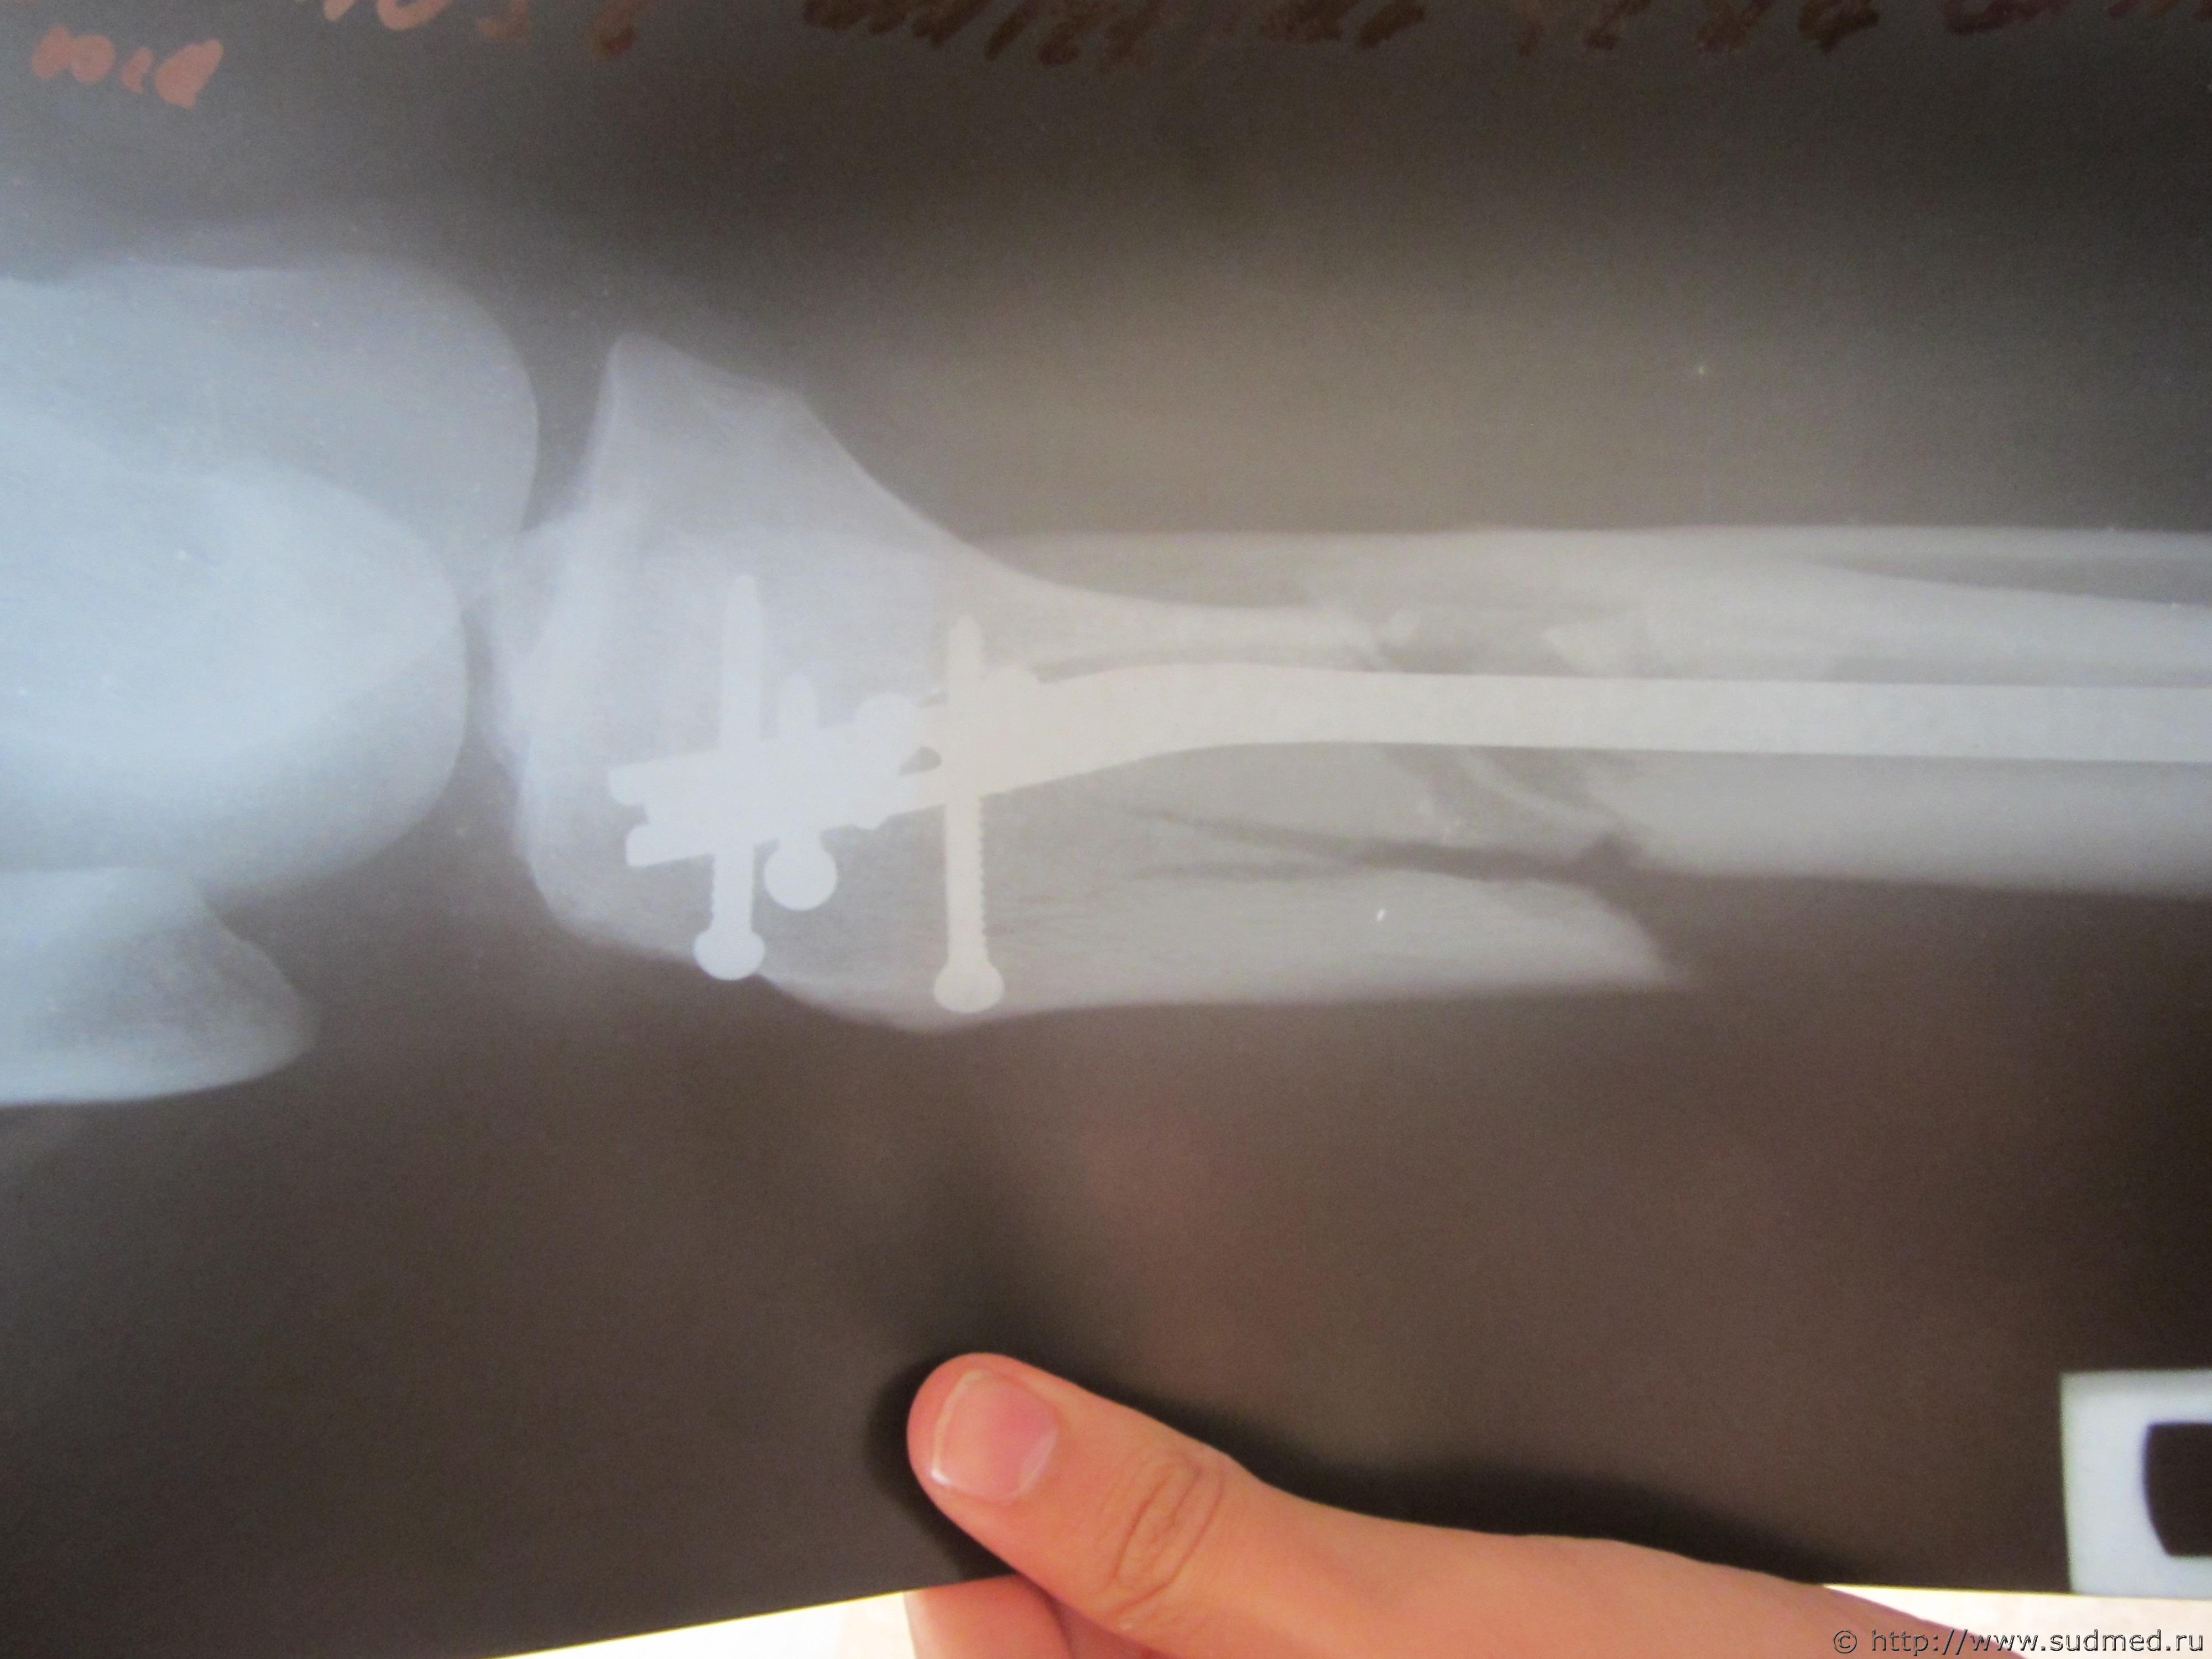

Выписка из истории болезни: Основной диагноз- закрытый оскольчатый перелом правой большеберцовой кости верхней трети со смещением осколков. Состояние на момент поступления- средней тяжести. Наложено скелетное вытяжение за пяточную кость. Лечение в стационаре- операция остиосинтеза правой большеберуовой кости блокированным штифтом.

Спасибо Вам заранее. Фоты прилагаю...

Судебная медицина - Прикрепленное изображение Судебная медицина - Прикрепленное изображение